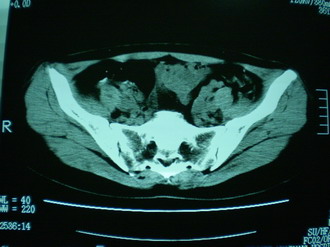

子宫增大,内可见类三角形低密度区,子宫后方可见类圆形团块状影,内部密度不均匀,可见靶样结构,结合病史考虑1子宫后方宫外孕(宫内假孕囊形成)2子宫肌瘤合并妊娠

子宫明显前倾,增大,宫颈增大呈分叶状。子宫直肠窝见不规则形水样低密度。(膀胱胀尿不理想)

考虑:1、宫颈部占位;

2、子宫直肠窝少量积液(盆腔炎所致)。

考虑:1、宫颈部占位(宫颈癌?);

2、子宫直肠窝少量积液。

1、前曲子宫,2、宫颈部占位?3、盆腔及右输卵管积液?宫内积血?4、左侧卵巢囊肿。

子宫明显前倾,增大,宫颈增大呈分叶状。子宫直肠窝见不规则形水样低密度。